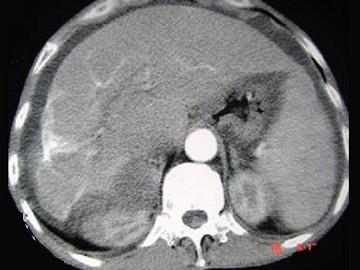

问题 男性,63岁,腹胀、双下肢水肿、乏力、食欲不振,影像所见如下图,最佳的诊断是 ( )

选项 A.酒精性肝硬化 B.血吸虫肝硬化 C.肝炎后肝硬化 D.局限性脂肪肝 E.原发性肝癌

答案 B